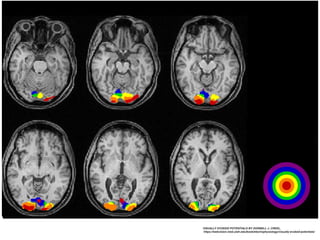

GENERATOR OF VEP - STRIATE AND PERI STRIATE CORTEX

VISUALLY EVOKED POTENTIALS BY DONNELL J. CREEL,

https://webvision.med.utah.edu/book/electrophysiology/visually-evoked-potentials/